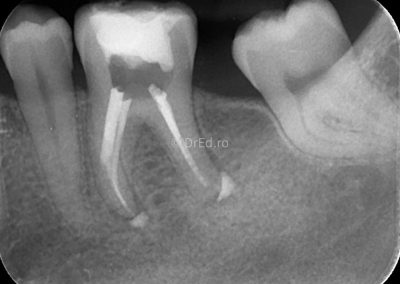

Galerie

Toate imaginile, fotografiile și radiografiile publicate pe acest site sunt protejate prin drepturi de autor și constituie proprietatea exclusivă a Dred.ro.

Aceste materiale sunt furnizate exclusiv în scop informativ și educațional și nu conțin date cu caracter personal sau informații care permit identificarea pacienților, în concordanță cu legislația privind protecția datelor cu caracter personal și GDPR.

Reproducerea, copierea, distribuirea, publicarea, transmiterea, modificarea sau orice altă utilizare, integrală ori parțială, a acestor materiale, în orice formă și prin orice mijloace, fără consimțământul prealabil scris al titularului drepturilor, este strict interzisă și poate atrage răspunderea civilă și/sau penală, în condițiile legii aplicabile privind drepturile de autor și protecția proprietății intelectuale.